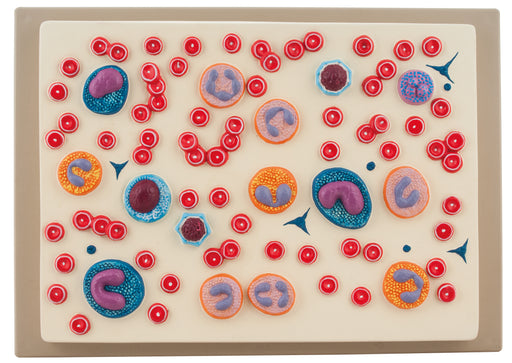

Red Blood Cell

Plaque mount shows erythrocytes, platelets and 5 types of leukocytes with their characteristic nuclei. Structures are numbered. Supplied with Engli...

View full detailsAM16036 -